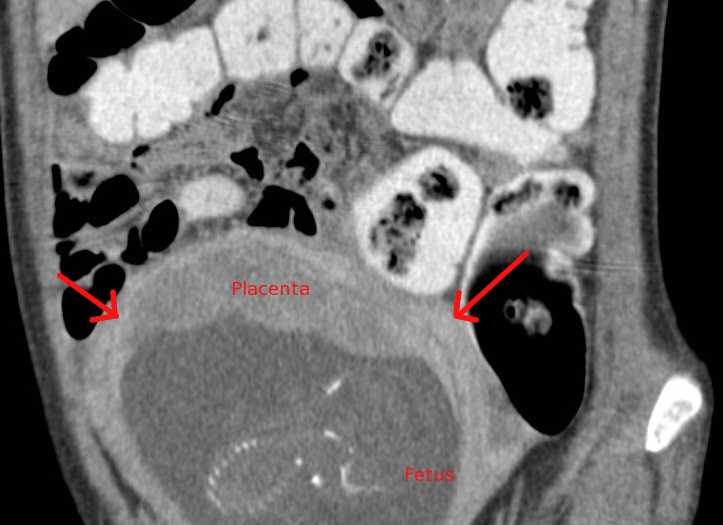

From www.ctisus.com

Intrauterine Pregnancy in a Trauma Patient OB/GYN Case Studies CTisus CT Scanning Is Ct Scan Bad For Pregnancy If intravenous contrast agent is used in ct, test thyroid function in the child after birth via heel prick. The radiologist (a doctor with expertise in medical imaging) and the ct technologist will adjust the ct exam. The increasing use of imaging in the population will inevitably result in an increase in requests for imaging in women who are pregnant. Is Ct Scan Bad For Pregnancy.